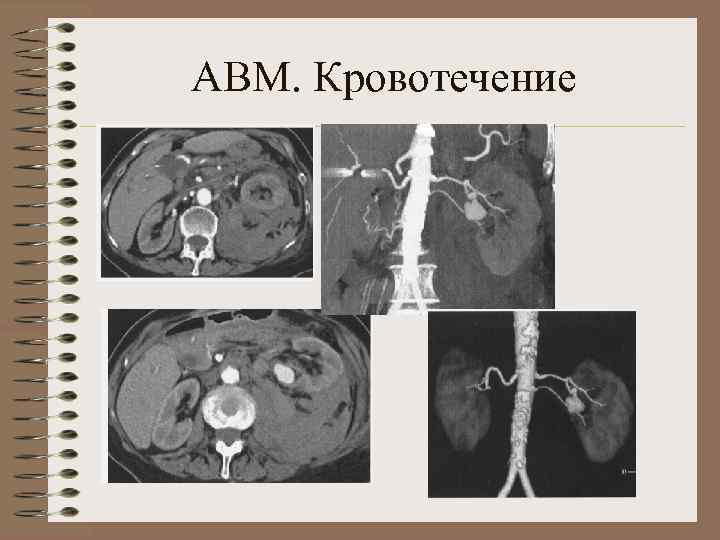

Аномалии почечных артерий 1. Аномалии положения и количества почечных артерий • Агенезия почечной артерии • Гипоплазия почечной артерии • Добавочная почечная артерия • Двойная почечная артерия • Множественные артерии 2. Аномалии формы и структуры артериальных стволов • А. аневризма почечных артерий • Б. фибромускулярный стеноз • В. Артерио-венозные фистулы

АВМ. Кровотечение